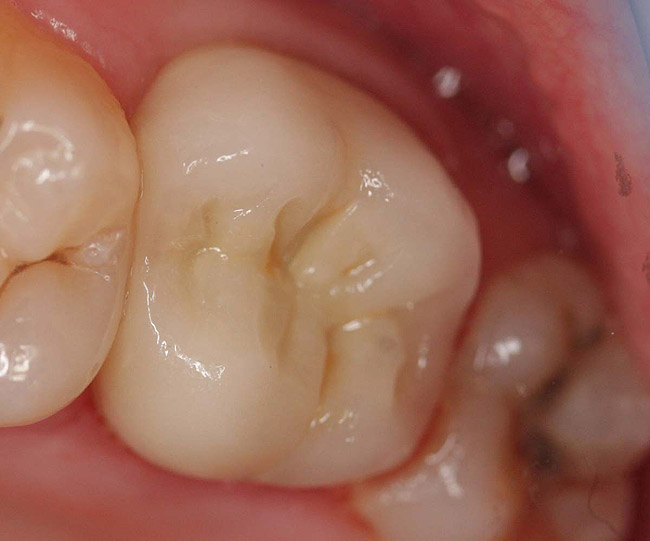

Figure 11  Final porcelain-fused-to-metal crown.

Figure 11